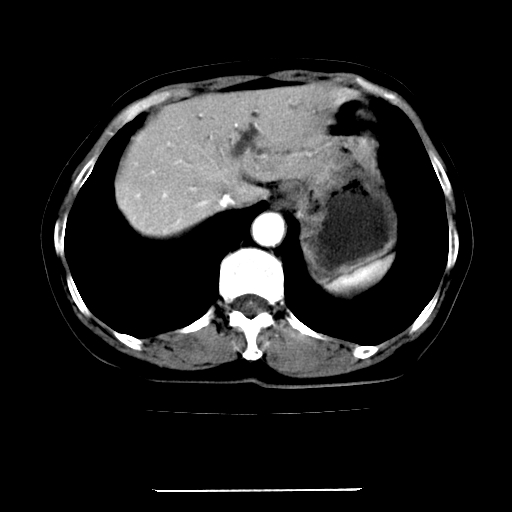

女,67岁,上腹部疼痛一周伴皮肤黄染,无发热。

左叶肝内胆管结石,并远端肝内胆管扩张。

支持肝内胆管结石并肝内胆管扩张。

肝内外胆管结石并肝内胆管扩张。

建议薄层观察,除外肝门部胆管细胞癌

考虑肝胆管癌;胰头占位?【形态失常,体积增大】

1、肝门高密度影下层面和胰头层面可见轻度胆管扩张,而静脉和延迟期均未见扫描完胰头,不能完全排除胰头占位。2、肝门部高密度影,考虑钙化或结石。

考虑肝门胆管癌伴门脉左支受侵包埋,建议mrcp进一步检查。